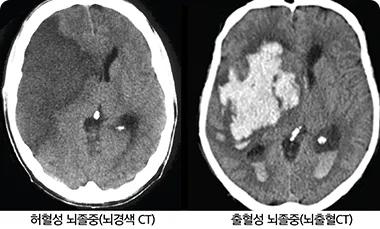

뇌경색에는 두 가지 주요 유형이 있습니다. 첫 번째는 허혈성 뇌경색으로, 대개 혈전이 혈관을 막아 발생합니다. 두 번째는 출혈성 뇌경색으로, 뇌혈관이 파열되거나 약해져 출혈이 발생하는 것입니다. 본 포스팅에서는 주로 허혈성 뇌경색의 초기 증상에 대해 설명드리겠습니다.